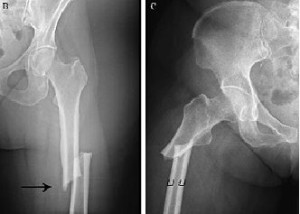

No se está tratando bien la osteoporosis luego de la fractura de cadera

23 julio 2018

Un estudio encuentra que menos del 10% de los pacientes había iniciado tratamiento para osteoporosis luego de 6 meses de la fractura, a pesar de los beneficios demostrados de los fármacos en esta indicación. JAMA Network Open, 20 de julio de 2018